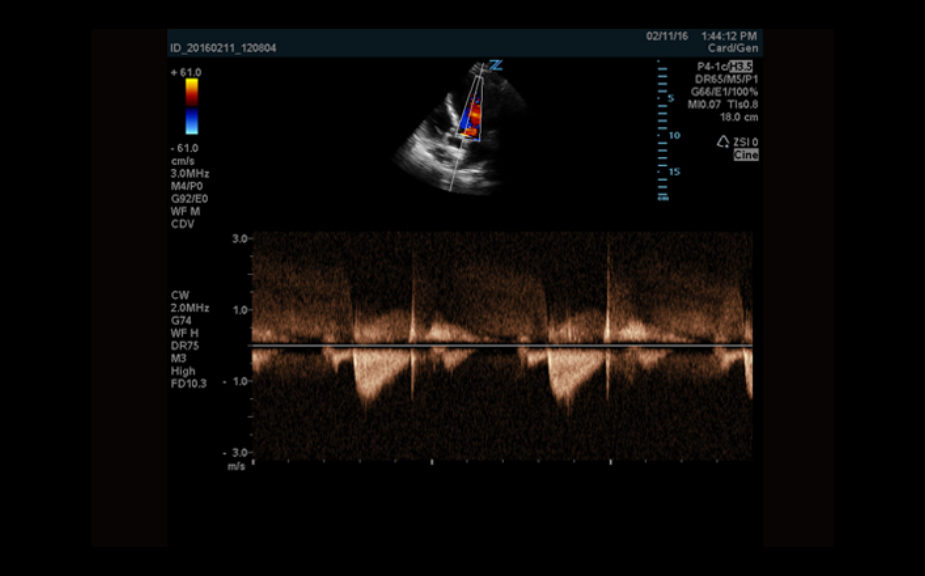

Equipped with patented, software based ZONE Sonography? Technology (ZST), the Z.One PRO provides optimally detailed B-mode and Doppler imaging for patients, regardless of body habitus, helping assure a reliable diagnosis.

- CW Doppler with auxiliary transducers

The Z.One PRO is powered by ZONE Sonography Technology, an innovative and proprietary image formation architecture that acquires and processes acoustic data up to ten times faster than conventional beamforming methods.